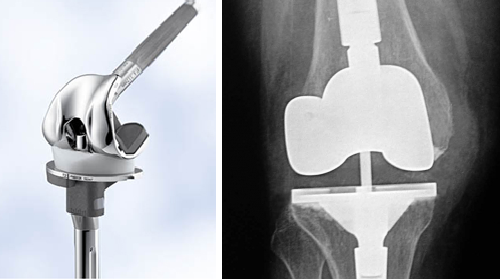

Thay khớp gối là một phẫu thuật cắt đi lớp sụn đầu xương đã bị hư hoại và thay vào đó là lớp mỏng kim loại bao bọc đầu xương tránh cho xương tiếp xúc trực tiếp với xương gây đau. Đồng thời thay khớp gối nhân tạo giúp chỉnh lại trục cơ học của chi dưới giúp áp lực phân bố đều hơn. Nên trước khi phẫu thuật ta thường thấy khớp gối bị vẹo vào trong nhưng sau phẫu thuật ta thấy gối và chân đã thẳng trở lại.

CẤU TẠO CƠ BẢN CỦA KHỚP GỐI NHÂN TẠO TOÀN PHẦN

Nhìn chung khớp gối có 3 thành phần cơ bản sau:

Thành phần xương đùi: được làm bằng kim loại bo tròn chung quanh đầu xương đùi. Có một rãnh giữa thành phần này cho phép xương bánh chè trượt lên khi co duỗi.

Thành phần xương chày: cấu trúc chứa mặt phẳng kim loại kèm với lớp chêm bằng nhựa cứng polyethylene (trọng lượng phân tử siêu cao: ultra-high molecular weight polyethylene). Cấu tạo hình dạng của thành phần polyethylene cũng thay đổi tùy thuộc vào lựa chọn phẫu thuật.

Thành phần bánh chè: là một tấm Polyethylene hình vòm đóng vai trò giúp xương bánh chè di chuyển trên rãnh thành phần xương đùi

Thành phần kim loại cấu tạo nên khớp gối nhân tạo thường là Titanium hoặc lõi Cobalt – Chromium tùy theo hãng sản xuất. Cobalt – Chromium là vật liệu phổ biến trong cấu tạo dụng cụ đặt vào cơ thể con người nhưng đã có ghi nhận các hiện tượng dị ứng với thành phần Cobalt – Chromium. Từ lâu Titanium được cho là ít gây dị ứng cho cơ thể con người tuy vậy ngày nay xuất hiện một số báo cáo dị ứng với Titanium.